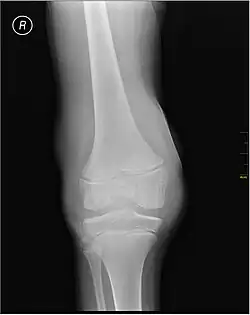

Synovial fluid analysis is another method to diagnose Hemarthrosis. It involves a small needle being inserted into the joint to draw the fluid.[6] Reddish-colored hue of the sample is an indication of the blood being present. Imaging tests are normally done. The tests also include MRI, ultrasound and X-ray test, which give better information about the joint inflammation.[7] Although MRI is superior method for this assessment, the US using the HEAD-US method performed by paediatric radiologists is a reliable tool for detection and quantification of haemophilic arthropathy in children in comparison to MRI.[8]